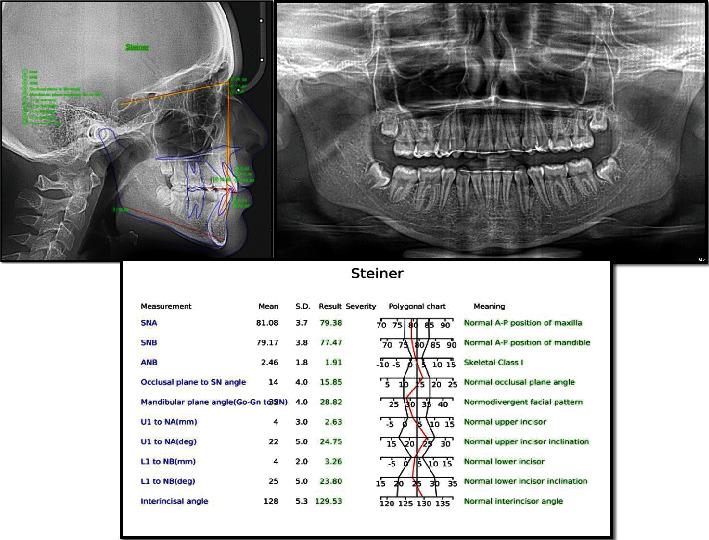

It is undeniable that the advent of extra-alveolar mini-implants for anchorage purposes has revolutionized the field of Orthodontics. This case report sheds light on an innovative anchorage plan using TADs, to carry out treatment for a 15-year-old female patient. The patient reported to the clinic with a chief complaint of rotated second premolars, crowding, and a deep bite. On examination, it was seen that the patient had a Class I skeletal pattern, Class II subdivision molar relationship, 90-degree maxillary second premolar rotations, crowding in both the arches, and a deep bite. In this case, the clinicians decided to use TADs for premolar derotation as it not only provides a pure rotational couple without any deleterious effects on the adjacent teeth but also helps shorten the overall treatment time. The total treatment time for this case was 10 months.

不可否认,用于支抗目的的牙槽外微型种植体的出现彻底改变了正畸领域。本病例报告揭示了一种使用微型种植体支抗(TADs)的创新支抗方案,用于治疗一名15岁女性患者。该患者到诊所就诊,主诉为第二前磨牙扭转、牙列拥挤和深覆合。检查发现,患者为I类骨骼型、II类亚类磨牙关系、上颌第二前磨牙90度扭转、上下牙弓均有拥挤以及深覆合。在本病例中,临床医生决定使用微型种植体支抗来纠正前磨牙扭转,因为它不仅能提供纯粹的旋转力偶,对相邻牙齿没有任何有害影响,还有助于缩短整体治疗时间。该病例的总治疗时间为10个月。